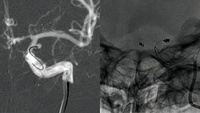

One&Done coiling for tiny aneurysms

In this challenging case of ruptured Acom and AchoA aneurysms, simple coiling with larger-volume, ultrasoft coils enabled stable occlusion in a single step, avoiding the risks of antiplatelet therapy and offering an elegant, efficient solution. [...]